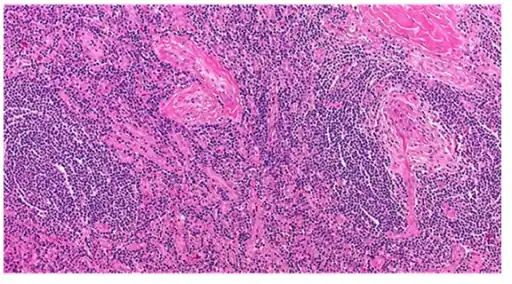

| Micrograph of lymph node biopsy demonstrating hyaline vascular features consistent with Castleman disease | |

Appearance of hyaline vascular type Castleman's disease (histology)

The microscopic appearance (histology) of biopsied tissue from an enlarged lymph node must demonstrate a constellation of features consistent with Castleman disease. There are three patterns of characteristic histologic features associated with UCD:[6]

- Hyaline vascular - regressed germinal centers, follicular dendritic cell prominence or displasia, hypervascularity in interfollicular regions, sclerotic vessels, prominent mantle zones with an “onion-skin” appearance.

- Plasmacytic – increased number of follicles with large hyperplastic germinal centers and sheetlike plasmacytosis (increased number plasma cells).

- Mixed - features of both hyaline vascular and plasmacytic patterns

UCD most commonly demonstrates hyaline vascular features; however, plasmacytic features or a mixture of both hyaline vascular and plasmacytic features may also be seen in UCD lymph nodes.[4] The clinical utility of subtyping Castleman disease by histologic features is uncertain, as histologic subtypes do not consistently predict disease severity or treatment response.[6]